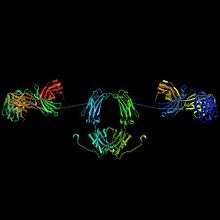

In secretory IgA, the form found in secretions, polymers of 2-4 IgA monomers are linked by two additional chains; as such, the molecular weight of slgA is 385,000D. One of these is the J chain (joining chain), which is a polypeptide of molecular mass 15kD, rich with cysteine and structurally completely different from other immunoglobulin chains. This chain is formed in the IgA-secreting cells.

The oligomeric forms of IgA in the external (mucosal) secretions also contain a polypeptide of a much larger molecular mass (70 kD) called the secretory component that is produced by epithelial cells. This molecule originates from the poly-Ig receptor (130 kD) that is responsible for the uptake and transcellular transport of oligomeric (but not monomeric) IgA across the epithelial cells and into secretions such as tears, saliva, sweat and gut fluid.

The high prevalence of IgA in mucosal areas is a result of a cooperation between plasma cells that produce polymeric IgA (pIgA), and mucosal epithelial cells that express an immunoglobulin receptor called the polymeric Ig receptor (pIgR). pIgA is released from the nearby activated plasma cells and binds to pIgR. This results in transportation of IgA across mucosal epithelial cells and its cleavage from pIgR for release into external secretions.[11]

Polymeric IgA (mainly the secretory dimer) is produced by plasma cells in the lamina propria adjacent to mucosal surfaces. It binds to the polymeric immunoglobulin receptor on the basolateral surface of epithelial cells, and is taken up into the cell via endocytosis. The receptor-IgA complex passes through the cellular compartments before being secreted on the luminal surface of the epithelial cells, still attached to the receptor. Proteolysis of the receptor occurs, and the dimeric IgA molecule, along with a portion of the receptor known as the secretory component, are free to diffuse throughout the lumen.[13] In the gut, IgA can bind to the mucus layer covering the epithelial cells. In this way, a barrier capable of neutralizing threats before they reach the epithelial cells is formed.